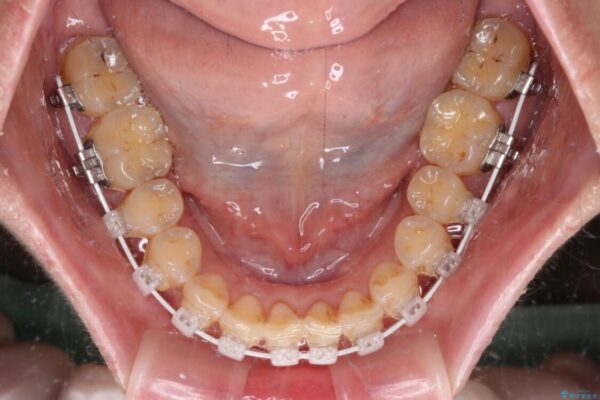

審美装置

なるべく早めに治療を終えたいとのことで、補助装置を用いて上顎臼歯を後方に移動させ、同時にワイヤー装置にて整えることとしました。

治療途中

• 【モニター】飛び出た前歯を整えたい ワイヤー矯正治療 治療途中画像